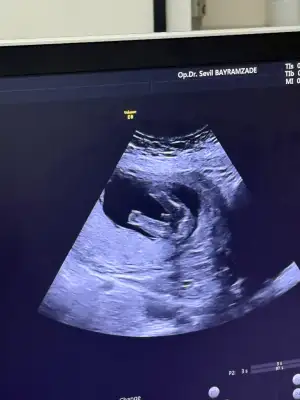

Günaydın kızlar sabah tesadufen devlette randevu bulup hastaneye gittim bebiş 21 cm olmuş 20 haftalık dedi sağlıklı şükür kaç gündür hareket etmiyor diyordum meğerse içerde kıpır kıpırmis 😂 hareket hissetmiyorum diyen arkadaşlar siz de endişelenmeyin bebişler haberimiz olmadan büyüyor ♥️♥️